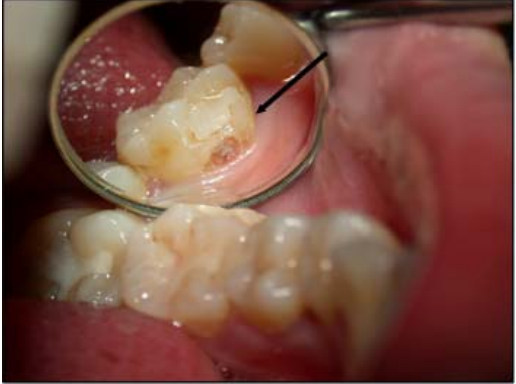

74. 根據美國疾病管制中心(Centers for Disease Control and Prevention, CDC)與美國各州及地區 牙醫行政官員協會(Association of State and Territorial Dental Directors, ASTDD)於2003年聯 合出版的基本篩檢調查方法(Basic Screening Survey),下圖箭頭所指的牙齒有臨時填補物, 應歸類為何項?

(A)未治療齲齒(untreated caries) (B)氟斑齒(dental fluorosis) (C)已填補(filled) (D)齲齒經驗(caries experience)